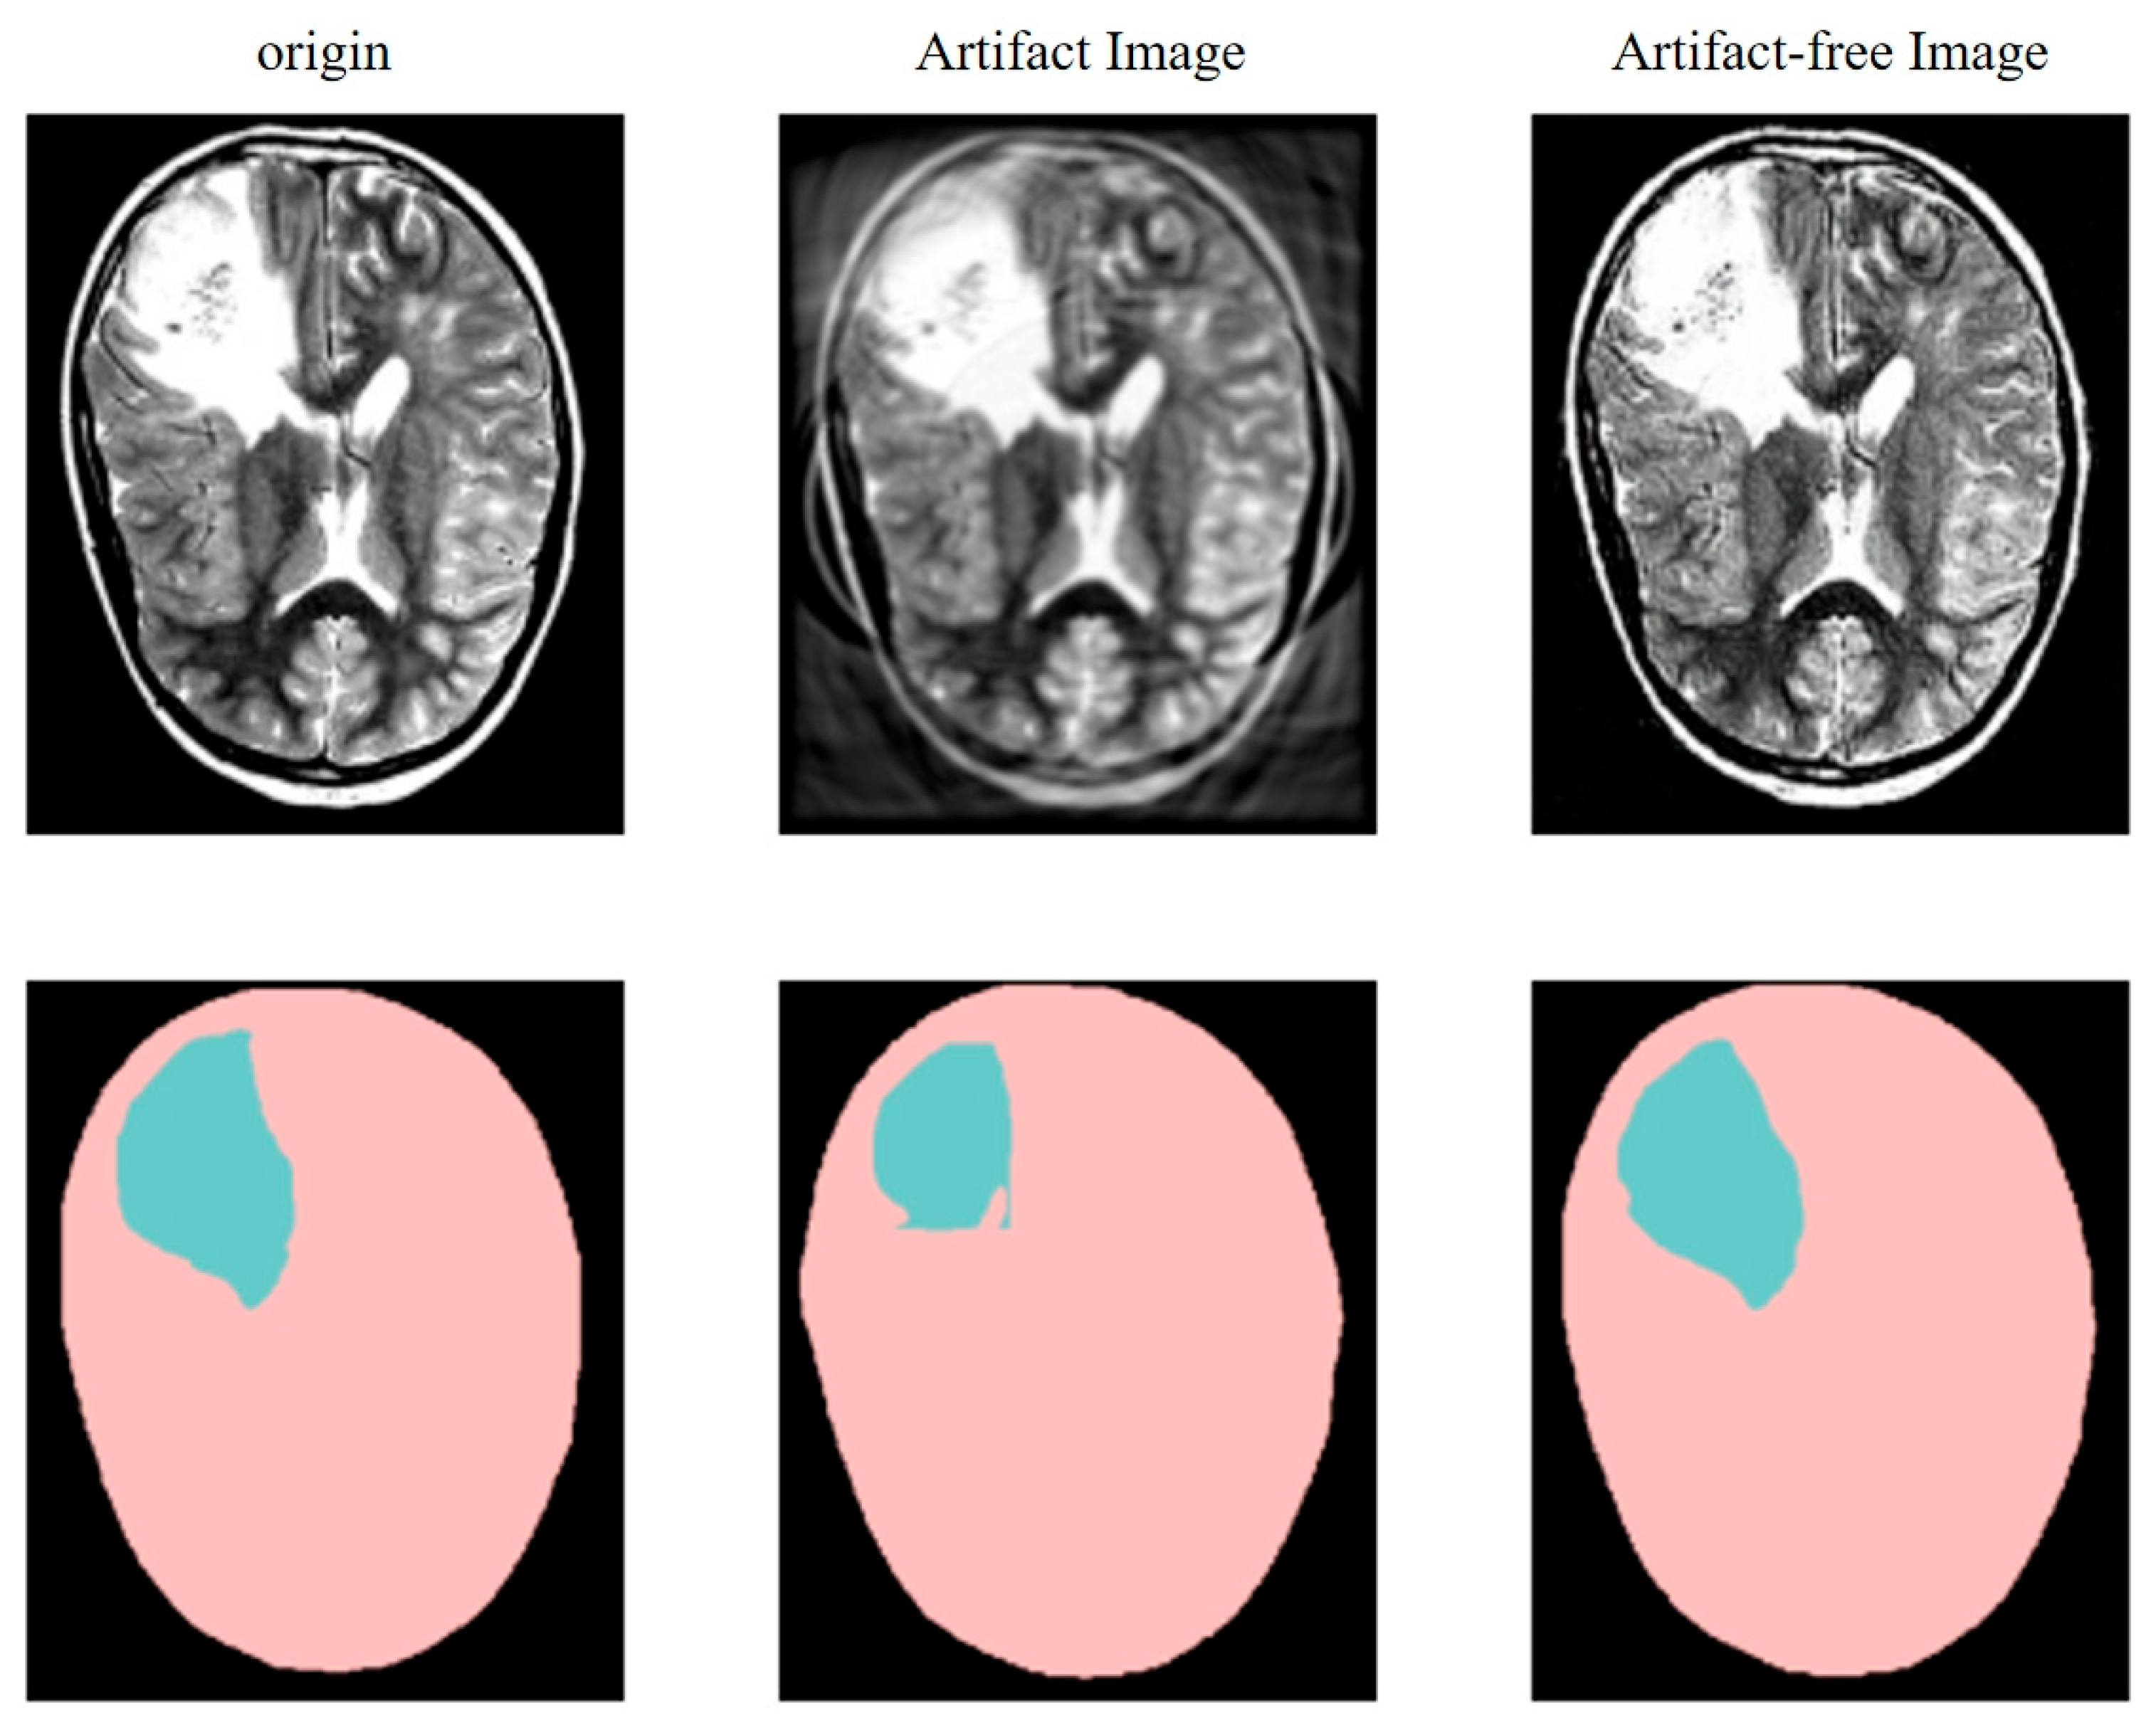

3.3.2. Photoacoustic Image Segmentation Experimental Results and Analysis

| Precision | Recall | Accuracy | IoU | Mean BFScore | Dice | ||

|---|---|---|---|---|---|---|---|

| Artifact Image | All | 0.915 | 0.852 | 0.961 | 0.773 | 0.863 | 0.864 |

| Brain tumor | 0.843 | 0.704 | 0.970 | 0.621 | 0.766 | 0.766 | |

| Brain | 0.986 | 1 | 0.952 | 0.924 | 0.961 | 0.961 | |

| Artifact-free Image | All | 0.955 | 0.932 | 0.986 | 0.946 | 0.972 | 0.973 |

| Brain tumor | 0.918 | 0.864 | 0.994 | 0.928 | 0.963 | 0.963 | |

| Brain | 0.992 | 1 | 0.978 | 0.964 | 0.982 | 0.982 |